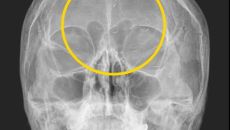

“기생충? 전기칩?”…60대 여성 머릿속 ‘이것’의 정체

60대 한국여성의 머릿속에서 기생충처럼 보이는 이물질이 흩어져 있는 엑스레이 사진이 공개돼 화제다. 의사이자 작가로 활동하고- 2025.03.13 06:00